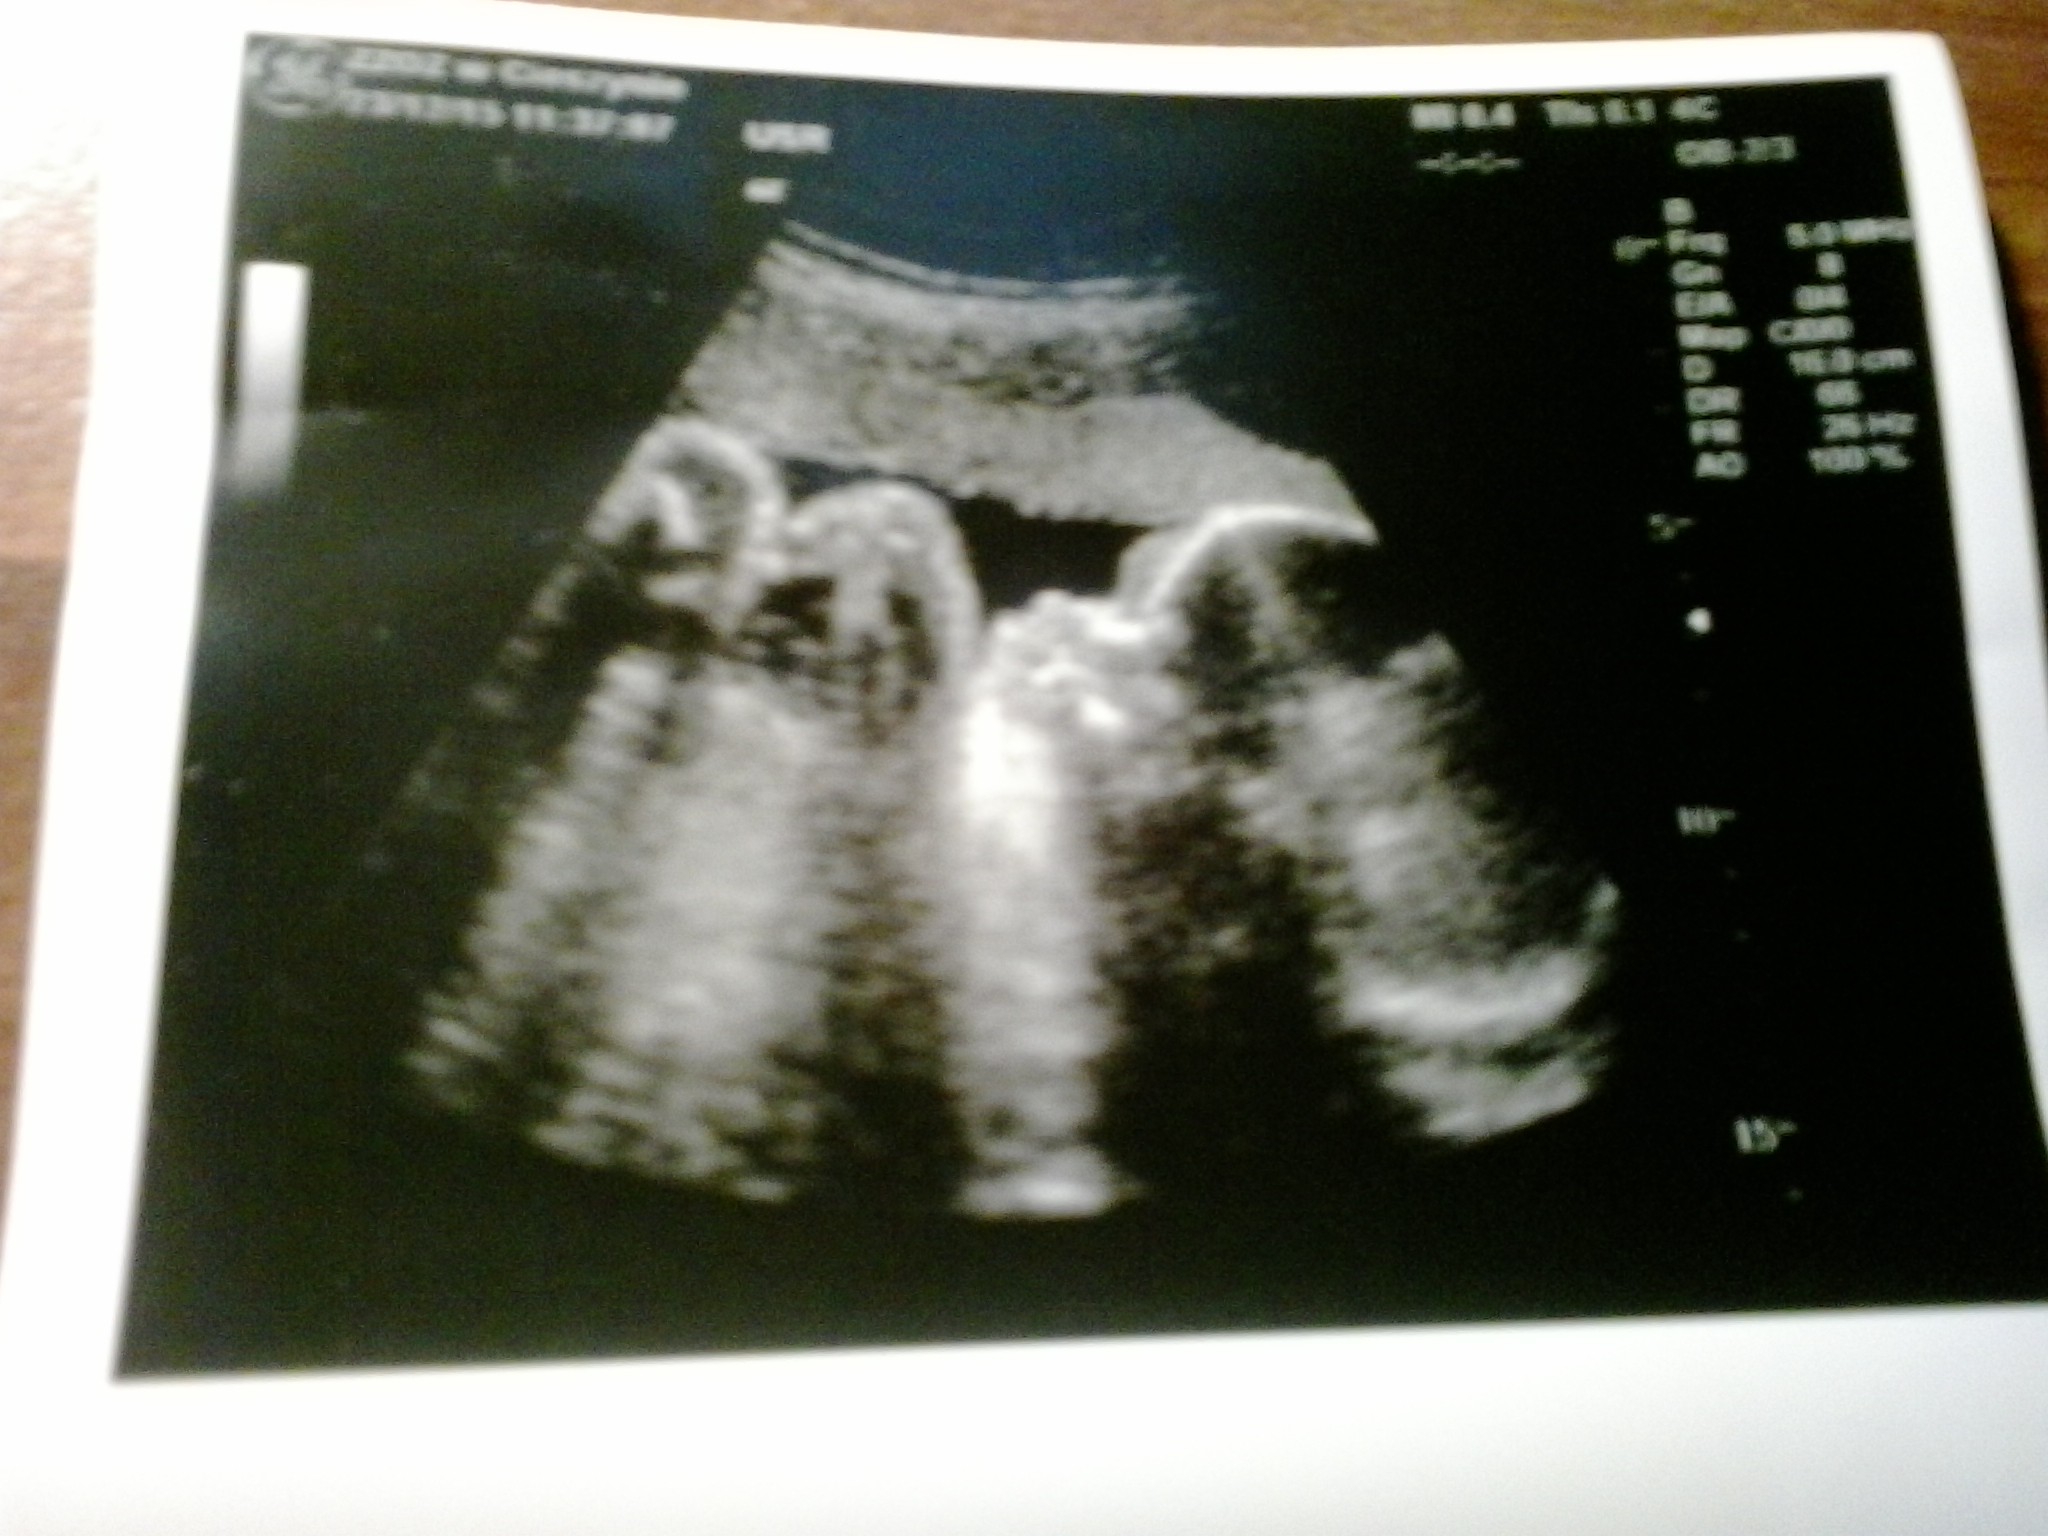

Szyjka dluga.zamknieta.Mala wazy 1100 g i proporcjonalnie co do OM.L4 dostalam do 20.01.Cisnienie ok

A to moja Milenka